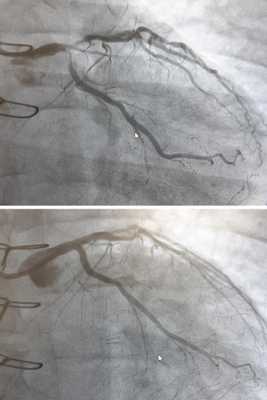

- Коронарография (КАГ). Считается одним из основных методов диагностики ББИМ из-за наличия доказанной прямой связи между заболеванием и стенозом коронарных артерий. Метод позволяет определить природу и степень сужения артерий сердца, установить, сколько и какие именно сосуды поражены, какова протяженность стеноза. Данные КАГ в значительной мере влияют на выбор метода лечения.

Проведение коронарографии в диагностике ишемической болезни сердца позволяет контрастировать сосуды миокарда и определять нарушения их проходимости, степень стеноза или окклюзии. Коронарография используется для решения вопроса об операции на сосудах сердца. При введении контрастного вещества возможны аллергические явления, в т. ч. анафилаксия.